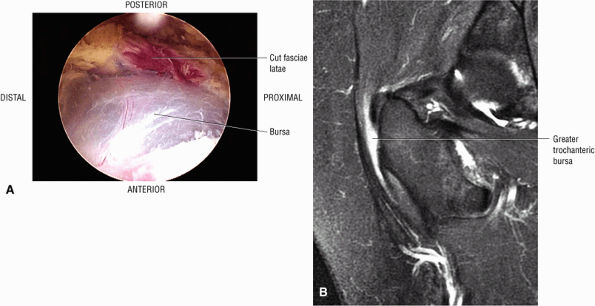

or secondary to communication with the hip joint. Trochanteric bursitis suspected on coronal images is confirmed on axial images.